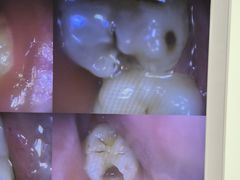

• 欢乐口腔(望京分院)

• -欢乐口腔(望京分院)